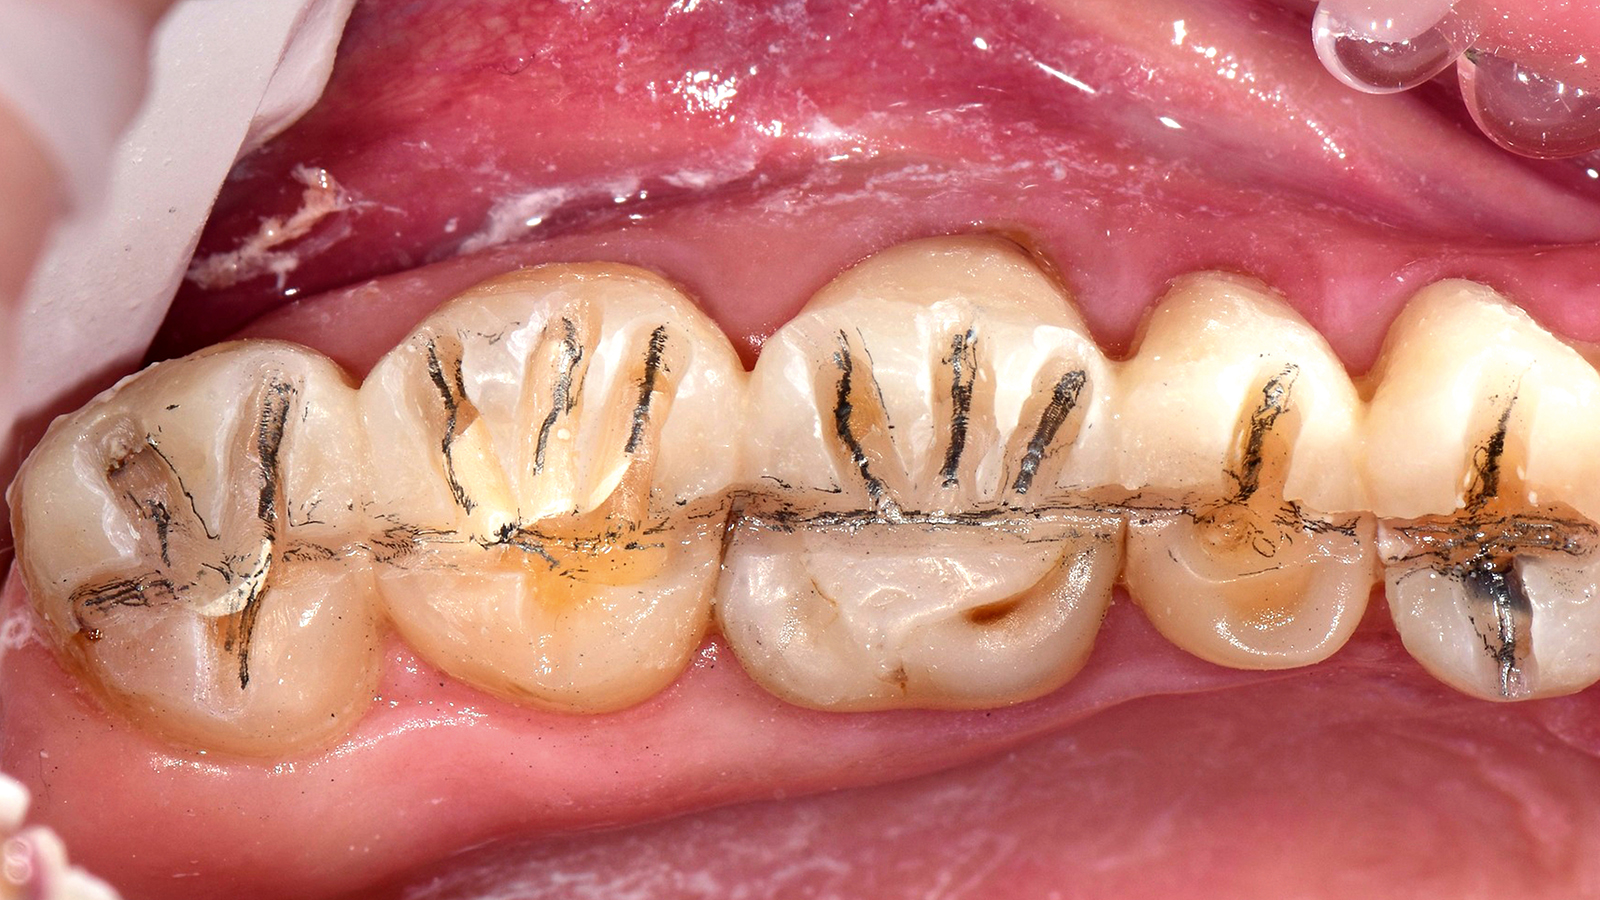

The ONE shade has been optimised to deliver the perfect balance of chroma and translucency that allows the restoration to become virtually invisible. Therefore, the ONE shade can be used with confidence in any Class I and Class II restoration. And this colour adaptation is what we call Adaptive Light Matching.

Charisma Diamond/ Charisma Topaz ONE Shade blends seamlessly into the surrounding dentition, independent of the tooth shade, enabling restorations to simply disappear. The universal composites for everyday restorations offer a new one-shade solution within the Charisma family for the majority of everyday cases.

Charisma Diamond/Charisma Topaz ONE Shade determines the shade of the restoration by absorbing the lightwaves that are reflected by the surrounding tooth shade.